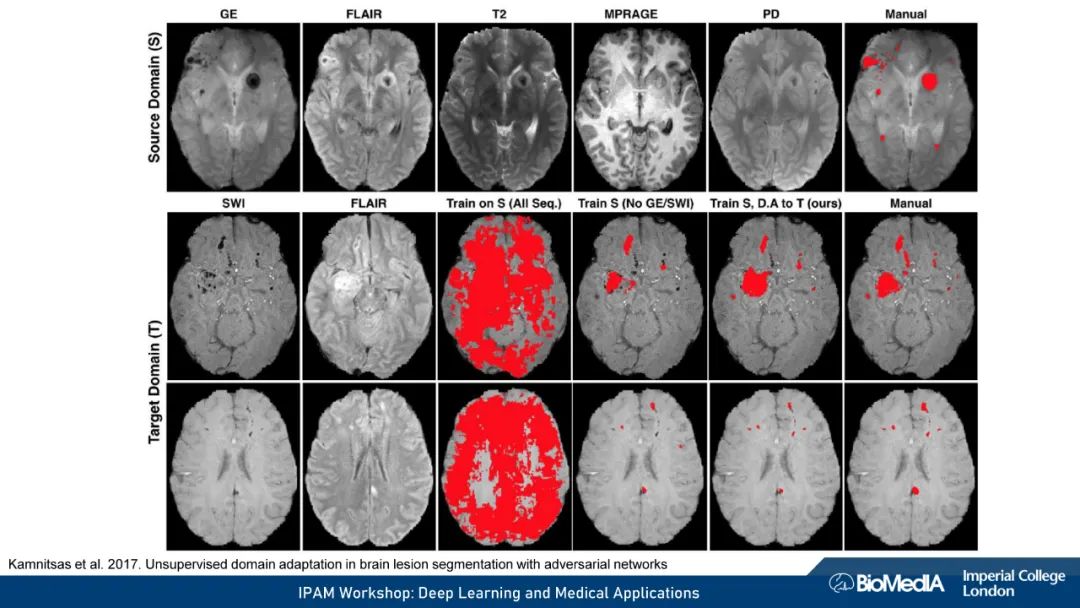

我们使用因果推理来阐明医学成像的关键挑战:1) 数据稀缺,即高质量注释的有限可用性 2) 数据不匹配,即训练有素的算法可能无法在临床实践中推广。我们认为,图像、注释和数据收集过程之间的因果关系不仅会对预测模型的性能产生深远的影响,甚至可能决定首先应该考虑哪种学习策略。例如,半监督可能不适合于图像分割——这可能是我们在医学图像分析中因果关系考虑的一个令人惊讶的见解。我们的结论是,对于基于机器学习的图像分析的成功至关重要的是,研究人员要能意识到并解释他们的数据背后的因果关系。